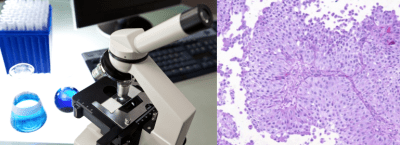

CITOLOGIA DE ORINA

Corresponde al estudio histopatológico de las células exfoliadas del urotelio. Tiene una mayor sensibilidad para la neoplasia de alto grado desde que la cohesión de las células de este tipo de tumor es débil.

La sensibilidad para el Carcinoma In Situ (CIS) es de un 28 – 100 %; para los tumores de Alto grado / G3 es de un 84 %; y para el Bajo grado disminuye a un 16 %.

La especificidad puede llegar a ser del 90 % y tiene una alta correspondencia entre patólogos.

Los falsos negativos corresponden a tumores Bajo grado y varían de un 40 a un 70 % de los casos.

Los falsos positivos corresponde a infección, inflamación, cuerpos extraños, litiasis, instrumentación e instilación intravesical.

Se discutira en el siguiente artículo de manera más extensa.

| La citología de orina es un estudio netamente histológico. |